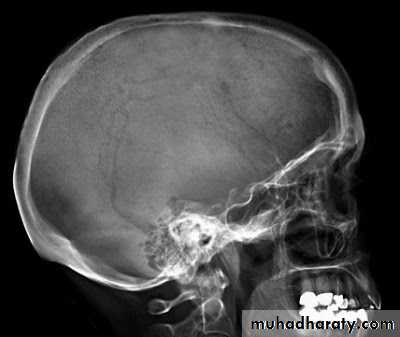

It runs medially with a slight anterior inclination.It is almost exactly in line with the internal acoustic meatus, and their shadows are superimposed in a true lateral radiograph of the skull.